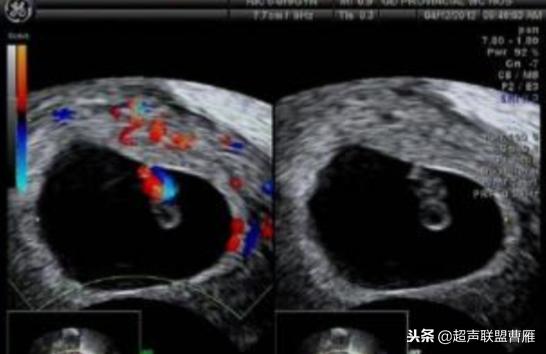

胎芽 卵黄囊 心管搏动信号

宫内早孕 (7周左右)